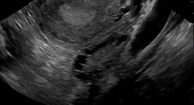

এ্যাপটেনাসিটিস কি? পরিশিষ্টটি পরিশিষ্টের প্রদাহ। এটি তীব্র বা দীর্ঘস্থায়ী হতে পারে। মার্কিন যুক্তরাষ্ট্রে অস্ত্রোপচারের ফলে পেটে ব্যথার সর্বাধিক প্রচলিত অ্যাকেনিডেটিসটি হয়। প্রায় 5 শতাংশ আমেরিকান তাদের জীবনযাত্রার কোনও স্থানে এ্যাপেক্সিসিটিস অভিজ্ঞতা লাভ করবে। Appendicitis যেকোনো সময়ে ঘটতে পারে, তবে এটি প্রায়শই 10 থেকে 30 বছরের বয়সের মধ্যে ঘটে। এটি মহিলাদের তুলনায় পুরুষের তুলনায় অনেক বেশি। … আরও পড়ুন আপনি Appendicitis সম্পর্কে জানতে চান সবকিছু